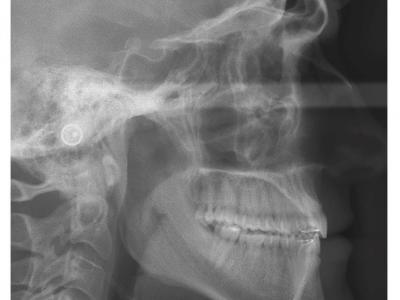

Les deux patients sont classe III squelettique (léger) avec un articulé inversé antérieur, mais avec des rapports de classe I molaire et des diastèmes.

Des dispositifs multi-attaches linguaux ont été choisis pour des raisons esthétiques et pour avoir des torques individualisés.

Le recul des incisives inférieures a permis la correction de l'articulé inversé et repositionné les lèvres (gain esthétique). Les torques ont été bien contrôlés avec des systèmes différents (le premier avec une insertion verticale de l'arc au niveau antérieur et le deuxième avec une insertion horizontale). Le contrôle du torque ne dépend donc pas du type d'insertion, mais du niveau d'insertion de l'arc dans les attaches (insertion au fond pour contrôler) et du jeu de l'arc dans ces dernières.

Dans le premier cas, une autre astuce a été de ne pas coller les attaches en lingual sur les 7 et de placer des sectionnels en vestibulaire sur les 6 et les 7 (gorges 022x028). L'intérêt est de ne pas avoir un arc en lingual dépassant lors du recul (et donc blessant), et d'augmenter le glissement au niveau des molaires en utilisant des gorges plus larges.